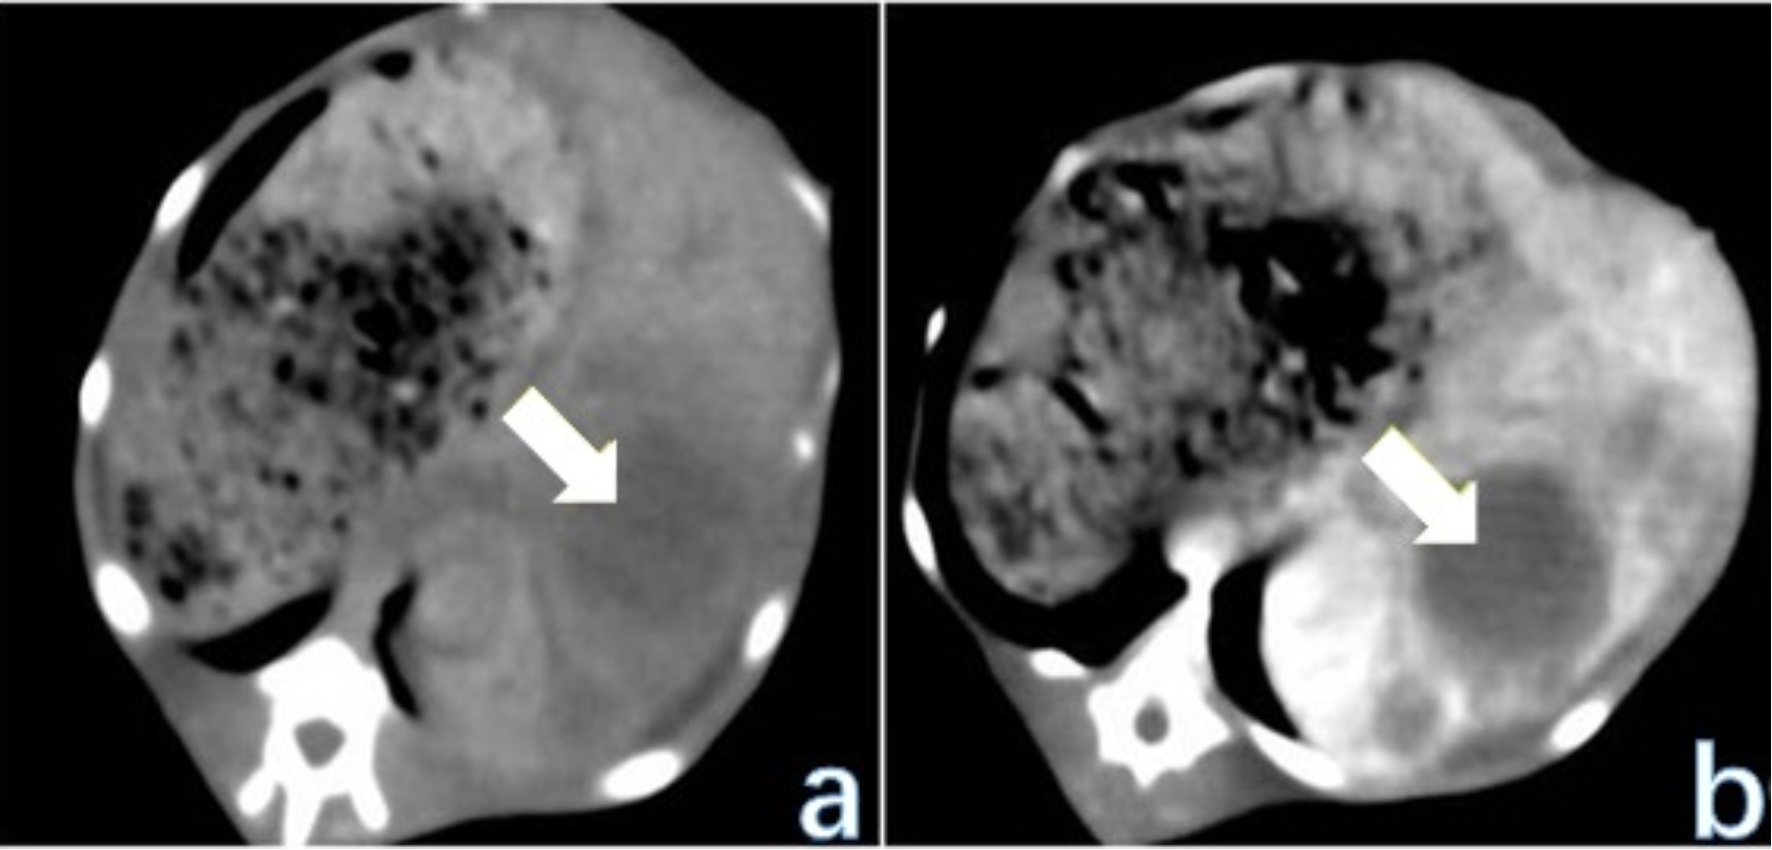

首先将荷瘤兔VX2肿瘤细胞株进行传代后获取瘤细胞悬浮液。依次将40只日本大耳兔在剑突中下部的左侧纵向切开暴露肝左叶,用眼钳将肝左叶完全拔出,将1 ml注射器换成18G穿刺针,并以30˚倾斜角插入肝左叶约1.5~2 cm,注入1 ml含有肿瘤颗粒的混合溶液,并用明胶海绵快速填充穿刺通道,腹腔喷庆大霉素40万U并压纱布伤口止血,逐层缝合腹部切口。术后三天连续注射庆大霉素8万U预防感染,术后单笼饲养。借助影像学手段判定模型构建是否达标,并对肿瘤的植入效果与生长状态展开评估[9],见图1

(a) 为CT平扫显示肝内不均匀低密度病灶,肿瘤中心密度较低;(b) 为CT增强扫描可见肿瘤边缘呈不均匀明显强化,中心坏死区不强化。

Figure 1. Liver CT scan of rabbit VX2 liver cancer animal model 4 weeks after tumor implantation

1. 兔VX2肝癌动物模型种植后4周行肝脏CT扫描